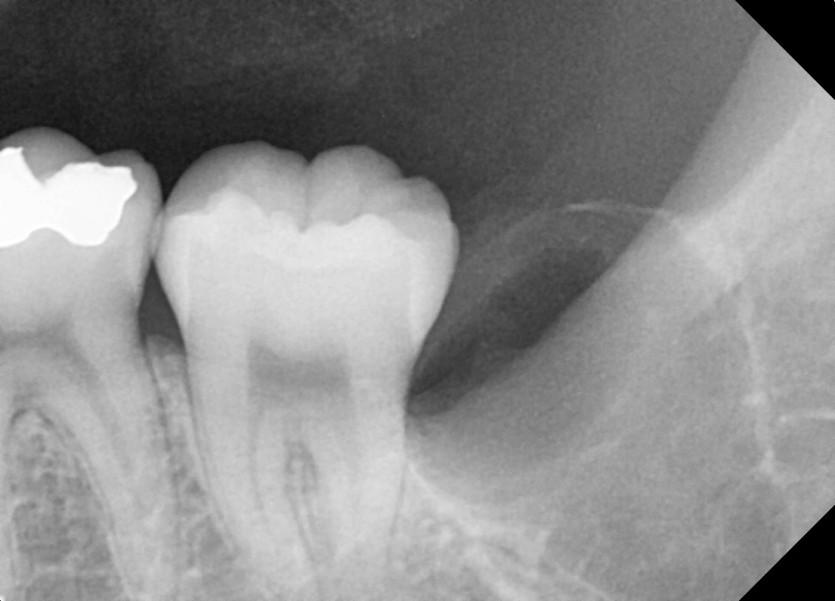

#38,48 사랑니 발치

구강 외과 전문의가 당일 발치했습니다.